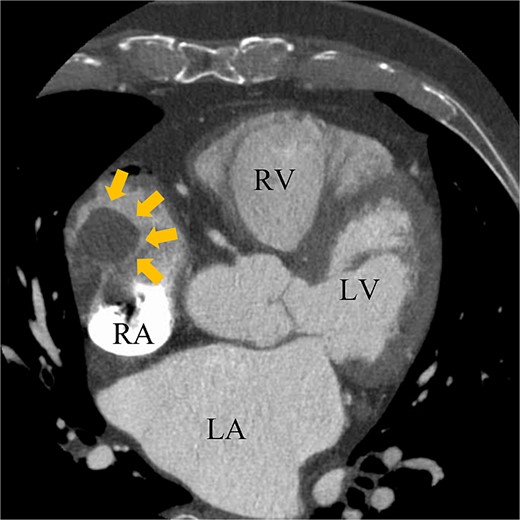

A 74-year-old male with a history of chronic atrial fibrillation (AF) for over 10 years, cardioembolic stroke, and cerebral hemorrhage, who had undergone LAA closure using the WATCHMAN device 1 year prior, was admitted after a follow-up contrast-enhanced CT scan revealed a 25-mm intracardiac mass in the right atrium (RA) (Fig. 1). After the WATCHMAN implantation, the patient was initially on direct oral anticoagulant (DOAC) but switched to dual antiplatelet therapy (DAPT) following the placement of a drug-eluting stent during percutaneous coronary intervention performed 9 months later. Transthoracic echocardiography revealed a left ventricular ejection fraction of 61% and a right atrial mass measuring 17 × 19 mm with slight mobility (Fig. 2). Despite anticoagulation therapy with heparin, the right atrial mass did not reduce in size. The patient decided to undertake surgical removal of the mass due to the potential risks of tumor or embolization. Additionally, contrast-enhanced CT showed a peri-device leak around the WATCHMAN device (Fig. 3). Considering the patient’s history of cerebral hemorrhage and the anticipated future cessation of anticoagulation therapy, we determined to perform WATCHMAN device explantation and LAA closure. Preoperative contrast-enhanced CT showed no thrombi attached to the WATCHMAN device and sufficient distance from the left circumflex artery (LCX) and the device (Fig. 4). We planned to remove the device by incising from the outside surface of the LAA. The Maze procedure was not performed because it was considered less effective due to the patient’s history of AF lasting more than 20 years and the presence of flat f-waves in lead V1 on the 12-lead electrocardiogram.

Preoperative enhanced computed tomography imaging showing a 25-mm intra-cardiac mass in the RA (arrows). RV, right ventricle; LA, left atrium; LV, left ventricle.